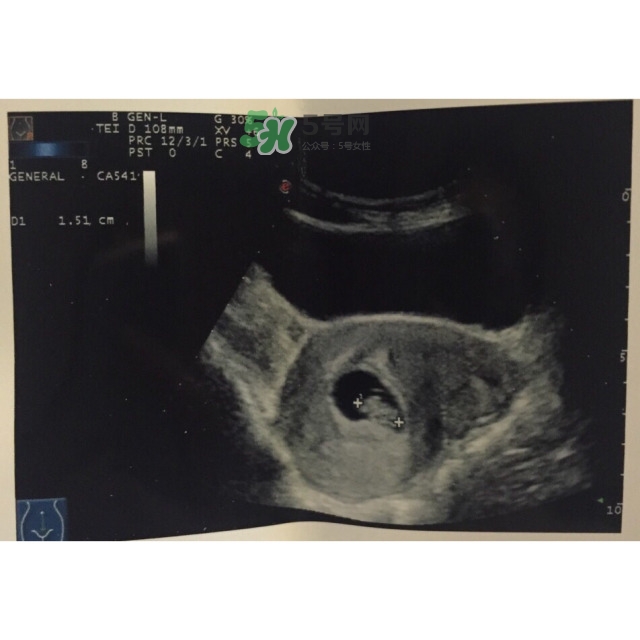

第一次做B超,胎兒太小,只見孕囊,未見卵黃囊和胚芽

* 2016年10月15日孕9W+6

第二次做B超,已見卵黃囊和胚芽